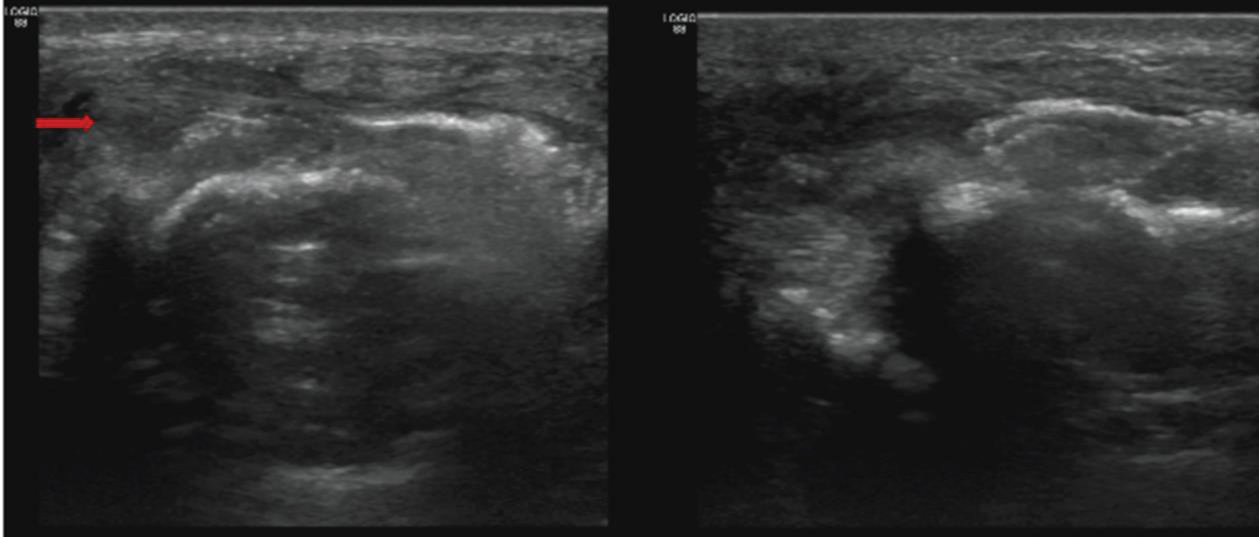

Given the lytic expansile lesion and the presence of adjacent soft

tissue, the clinician recommended a guided biopsy. An ultrasound

(USG) showed the bone lesion with associated soft tissue component

[Figure 3].Under aseptic precaution and local anesthesia ultrasound

Figure 3:Axial and sagittal axis ultrasound image showing irregularities

in the bone cortex with focal disruption. The soft tissues surrounding the

affected area exhibit thickening, indicating possible inflammation or fibrosis.

No significant fluid accumulation is seen in the soft tissues.